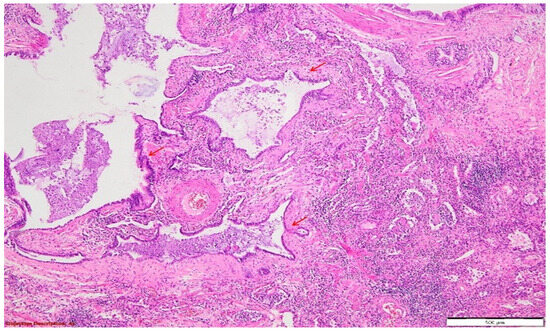

Figure 7. Pulmonary tissue with an enlarged bronchiolar lumen (bronchiectasis →), containing mucus and rare inflammatory elements; smooth muscle hyperplasia of the arterial media, and important polymorphous inflammatory infiltrate (predominantly lymphocytic) in the peri-bronchiolectatic interstitial parenchyma. HE, 40×.